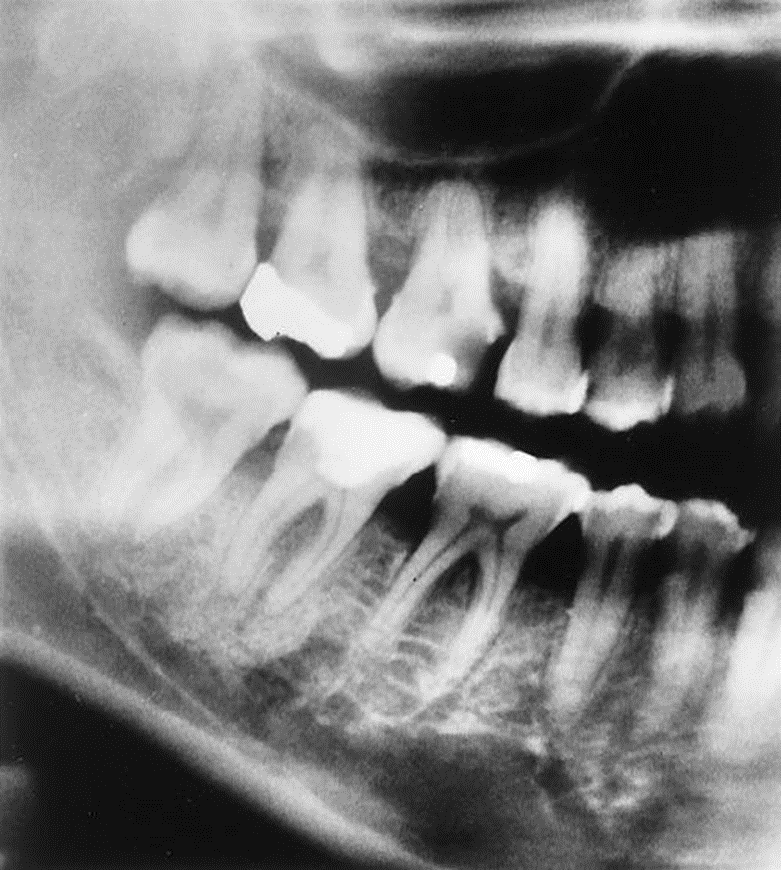

1. Mary is a 67-year-old who was referred to the periodontist. As part of the adiographic examination, this small radiolucent lesion was detected. The teeth were vital. Considering the patient’s age and the location, size, and clinical findings, what is your diagnostic impression?